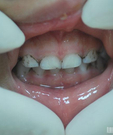

孩子的笑容是給家長最欣慰的回報,看著自己的孩子開心的笑時別提多幸福了,可偏偏現在的孩子很多都是一口“小黑牙”。那么小孩的牙齒為什麼發黑呢?

當牙齒表面本身粗糙、牙齒排列不齊時,不容易清潔乾淨,食物殘渣、色素會更容易附著在牙齒上,導致色素容易沉著。而牙齒被蛀壞之後,牙齒表面將變得更不平整,促使色素沉著變得更嚴重。

牙齒變黑